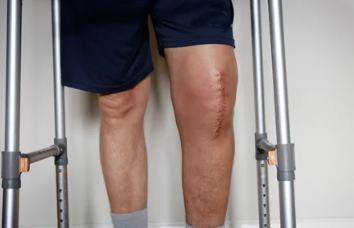

나이가 들면서 무릎 통증이 심해지고 일상생활이 힘들어지는 경우, 의사로부터 무릎 인공관절 수술을 권유받는 경우가 많다. 하지만 수술 비용이 부담되어 망설이는 분들도 적지 않다. 다행히도, 정부에서는 경제적으로 어려운 어르신들을 위해 무릎 인공관절 수술비 지원 제도를 운영 중! 그렇다면 지원 대상은 누구이며, 신청 방법은 어떻게 될까?

✔ 퇴행성 관절염이 심해지면 무릎 연골이 닳아 뼈끼리 부딪히며 심한 통증 유발

✔ 일상생활이 어려워지고 걷기조차 힘들어질 수 있음

✔ 수술을 통해 손상된 관절을 인공관절로 대체하면 통증 완화 & 활동 가능

✔ 하지만, 수술비가 평균 300~500만 원 정도로 부담이 클 수 있음